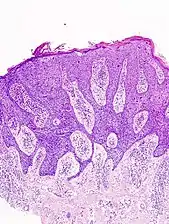

In situ disease

Bowen's disease is essentially equivalent to and used interchangeably with cSCC in situ, when not having invaded through the basement membrane.[12] Depending on source, it is classified as precancerous[13] or cSCC in situ (technically cancerous but non-invasive).[47][48] In cSCC in situ (Bowen's disease), atypical squamous cells proliferate through the whole thickness of the epidermis.[12] The entire tumor is confined to the epidermis and does not invade into the dermis.[12] The cells are often highly atypical under the microscope, and may in fact look more unusual than the cells of some invasive squamous-cell carcinomas.[12]